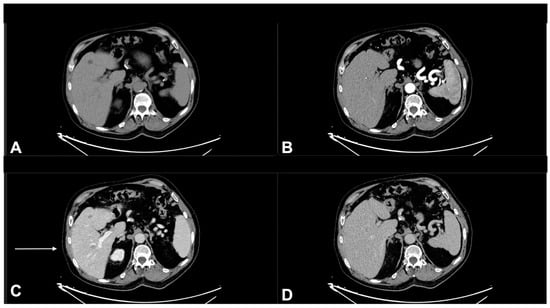

- Lim, A.M.; Cavanagh, K.; Hicks, R.J.; McLean, L.; Goh, M.S.; Webb, A.; Rischin, D. Delayed Response After Confirmed Progression (DR) and Other Unique Immunotherapy-Related Treatment Concepts in Cutaneous Squamous Cell Carcinoma. Front. Oncol. 2021, 11, 656611. [Google Scholar] [CrossRef]

- Chiou, V.L.; Burotto, M. Pseudoprogression and Immune-Related Response in Solid Tumors. J. Clin. Oncol. 2015, 33, 3541–3543. [Google Scholar] [CrossRef]

- Borcoman, E.; Kanjanapan, Y.; Champiat, S.; Kato, S.; Servois, V.; Kurzrock, R.; Goel, S.; Bedard, P.; Le Tourneau, C. Novel patterns of response under immunotherapy. Ann. Oncol. 2019, 30, 385–396. [Google Scholar] [CrossRef]